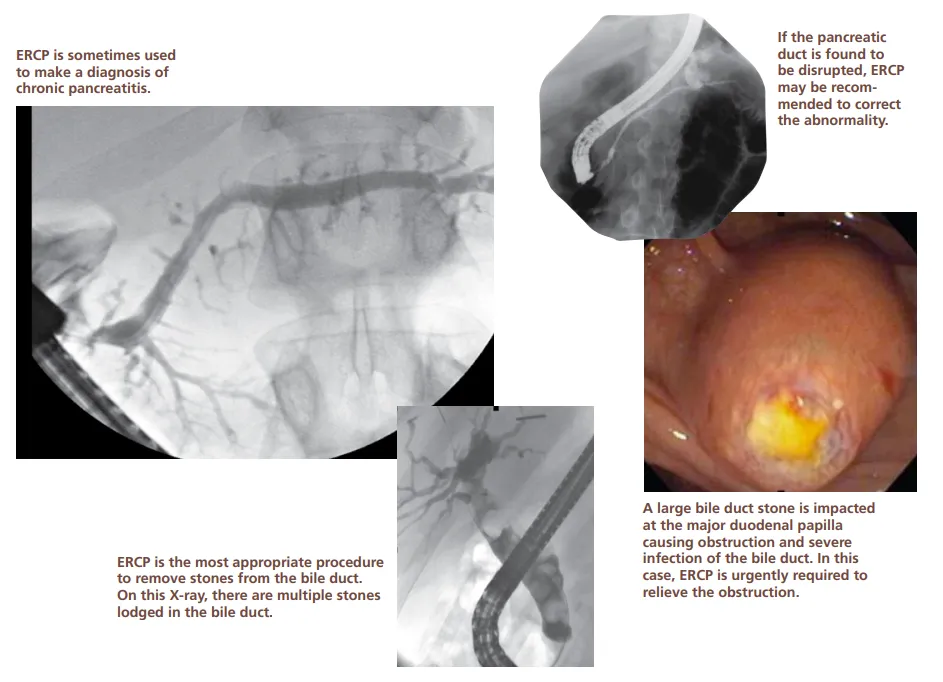

During ERCP, your doctor will pass an endoscope through your mouth, esophagus and stomach into the duodenum (first part of the small intestine). An endoscope is a thin, flexible tube that lets your doctor see inside your bowels. After your doctor sees the common opening to the ducts from the liver and pancreas, called the major duodenal papilla, your doctor will pass a narrow plastic tube called a catheter through the endoscope and into the ducts. Your doctor will inject a contrast material (dye) into the pancreatic or biliary ducts and will take X-rays.